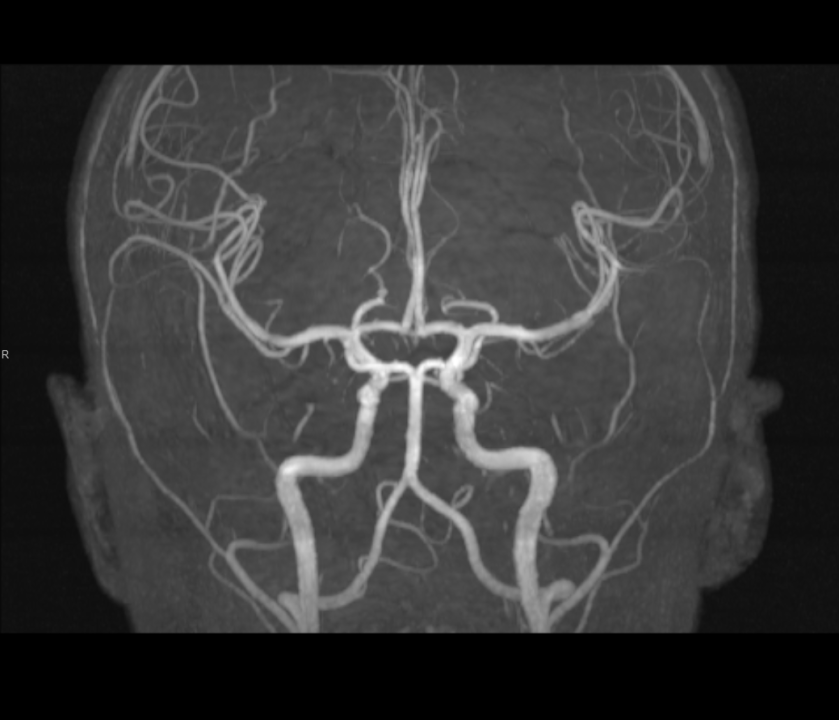

Tijekom Tjedna mozga Poliklinika Affidea Vita daje 20 posto popusta na magnetsku rezonancu!

MR angiografija